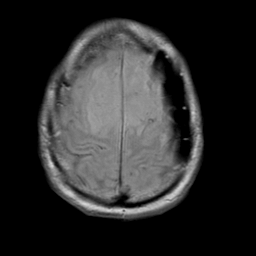

Meningioma, MR Study #2 -- Slice #17

[Home][Help][Clinical] Slice 17